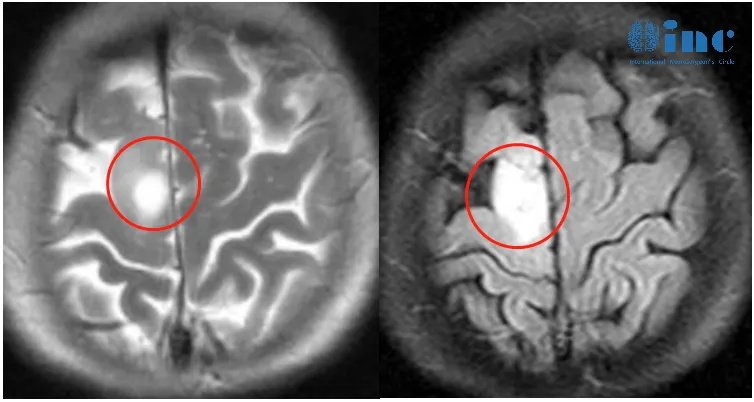

▼患者术前情况:2023年1月底罗女士突然左腿失去知觉摔倒,后面又类似情况发生几次。3月份,他们来到当地医院进行检查,颅脑MR+增强显示:右侧额叶异常信号灶,考虑低级别胶质瘤。当地医生建议:目前肿瘤比较小,手术怕伤到运动神经,也怕切不干净,先保守治疗,等腿和手的功能都出现障碍了,为了维持生命延长生存期不得已时再做手术。

此时正恰逢2023年巴教授春季中国行期间,他们便立马联系上INC医学顾问祖木医生,紧急整理资料咨询巴教授。巴教授回复:“切除率将接近全切(所以实际上可以达到胶质瘤的全切)”